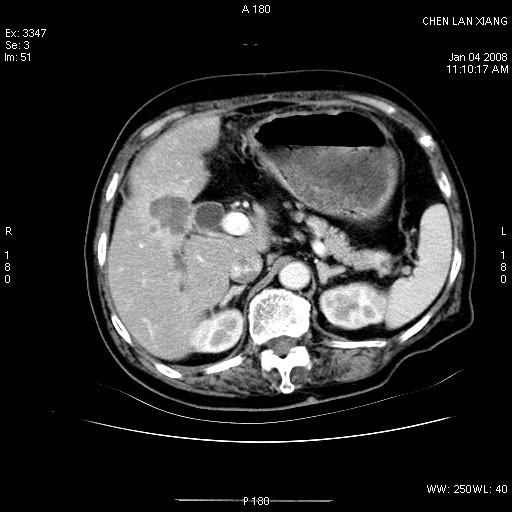

女,76岁,腹痛3-4天,b超示:肝内实性肿物,胆囊强回声,胆总管扩张.

胆囊内结增强影,肝内胆管、胆总管扩张明显。肝内胆管、胆总管下段多发结石,胆囊癌,建议mrcp检查

肝内外胆管多发结石;胆囊癌;

ct所见:1、 肝内胆管结石,肝内外胆管扩张。低位胆道梗阻,胆总管下端结石;2 胆囊扩大,胆囊壁不规则增厚

考虑:胆总管下端结石并肝内外胆管扩张,肝内胆管结石;

1)胆囊癌伴肝脏转移。2)胆总管下端结石、肝内胆管结石伴肝内外胆管扩张。